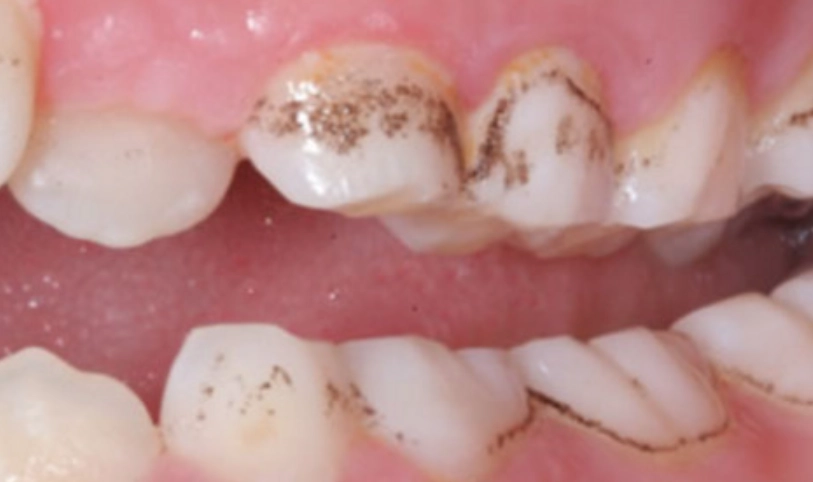

你可以把牙菌斑想像成一個由細菌、食物殘渣和唾液組成的黏性薄膜,它無色或淡黃色,緊緊貼在牙齒表面,尤其是牙齦溝和牙縫這些牙刷很難徹底清潔的地方。它不是吃飽飯馬上出現,而是大約飯後4到12小時開始形成。

最麻煩的一點是,如果沒有及時清除,牙菌斑裡的細菌會分解食物中的糖分,產生酸性物質。這些酸會腐蝕牙齒琺瑯質,蛀牙就來了。同時,牙菌斑如果堆積在牙齦邊緣,會刺激牙齦發炎,紅腫流血,這就是牙齦炎。再放任下去,發炎往牙根深處走,破壞牙周組織,變成牙周病,牙齒就可能開始搖動。

我常跟病人說一個比喻:牙菌斑就像浴室磁磚縫的皂垢,每天輕輕刷洗很容易掉,但放著不管幾天,它就會硬化成頑固的污漬(變成牙結石),這時非得用專業工具(洗牙)才清得掉了。